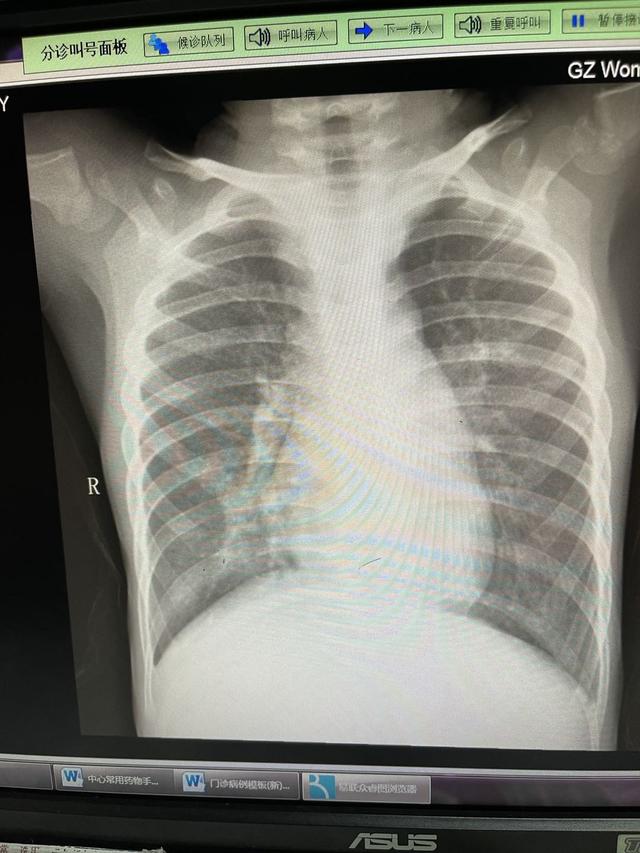

由于大部分人是在发热门诊,拍片的人非常少。于是我们拍了史上最快的一次片子,新生儿三凹征图片,前后15分钟,结果就出来了。

但定睛一看典型结果:支气管肺炎,如下图所示是什么:

不由得心中一紧。

医生拿到肺炎片子,留出一丝为难的神色,说道:“肺炎,这个需要输液治疗。不过呢,现在市妇幼只能留观,观察一个晚上,然后第二天也不能住院,要去人民路院区住院,早点过去应该能排上队”。